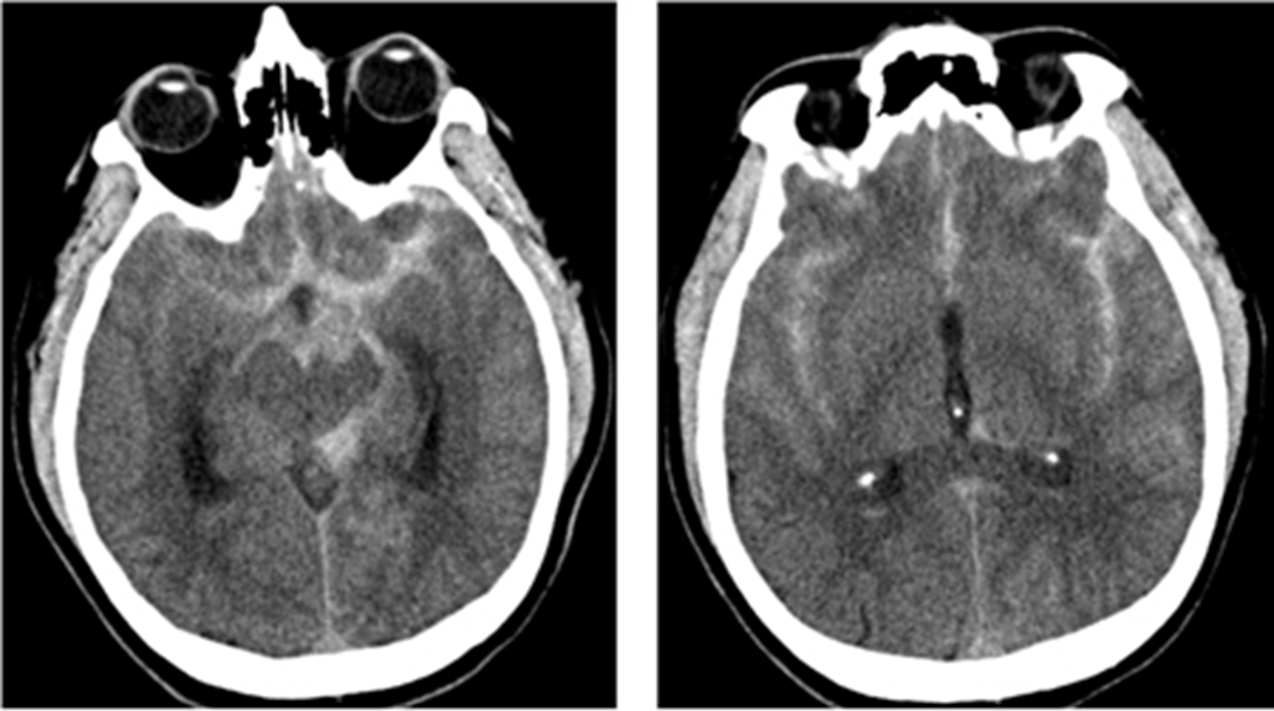

What do Subarachnoid Hemorrhages appear like on imaging? What additional tests might you do?

Subarachnoid hemorrhages will often present with a star sign on CT imaging

1) Star sign is where blood from subarachnoid hemorrhages tracks up in between the hemispheres of the brain, laterally between the sylvian fissure, and posteriorly to the midbrain

→ can often see blood accumulating in the sylvian fissure bilaterally